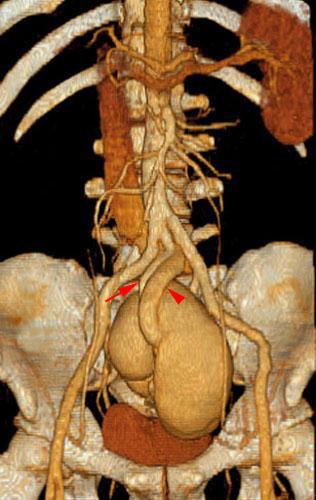

Hipoplasia renal 2